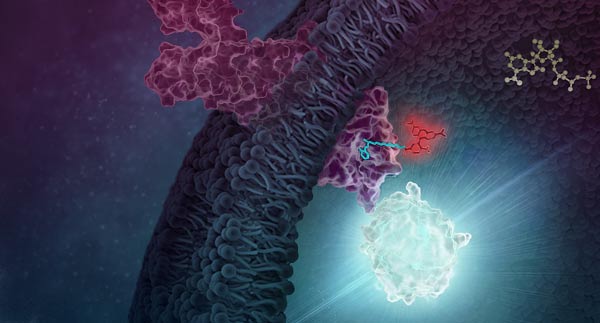

Measure Ligand Binding in Live Cells

NanoBRET® target engagement is a highly sensitive and quantitative method for measuring ligand binding. This involves labeling the GPCR with a HiBiT tag (via transient transfection or CRISPR/Cas9) and labeling the ligand with a fluorophore. When the ligand binds to the GPCR, their close proximity generates energy transfer, resulting in a fluorescence signal that enables precise quantification.